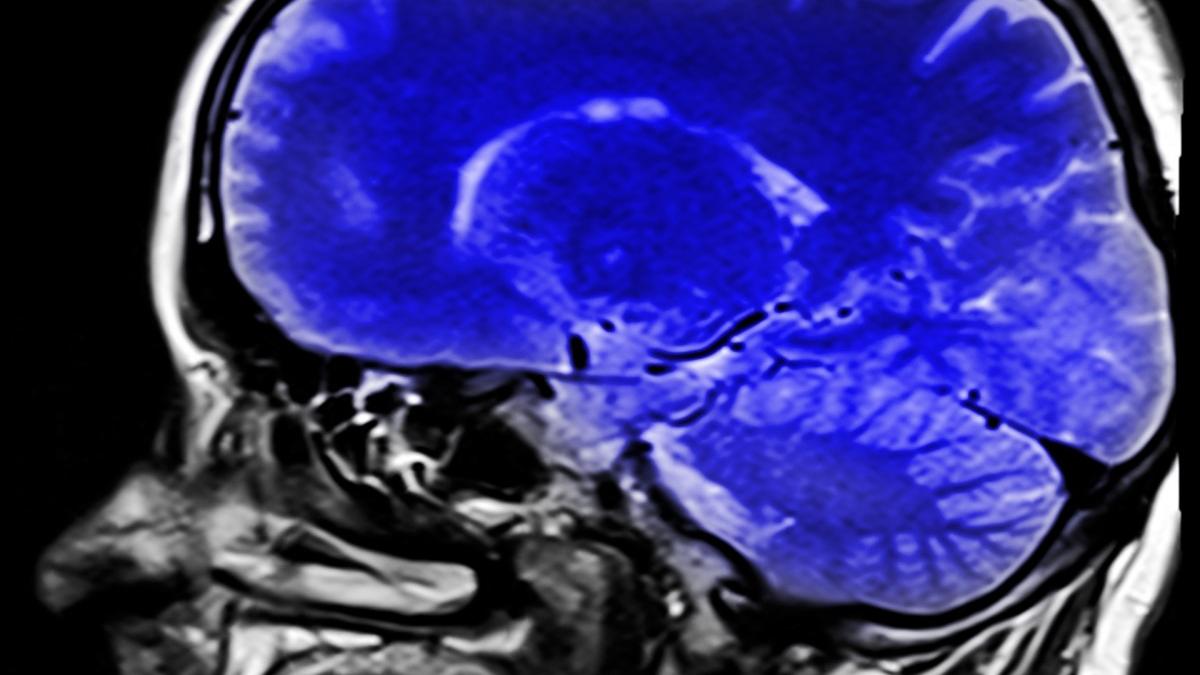

Anorexia micşorează creierul, arată un nou studiu

O tulburare alimentară des întâlnită în zilele noastre și potențial mortală are efecte nebănuite asupra organismului, mai cu seamă asupra creierului. Un nou studiu subliniază că anorexia modifică structura creierului, slăbind sănătatea acestuia. În plus, îl şi micşorează.

Pe baza unui total de 1.648 de scanări ale creierului feminin (685 cu anorexie nervoasă) colectate din 22 de locații diferite, cercetătorii au descoperit scăderi ale grosimii corticale, volumelor subcorticale și suprafeței corticale la persoanele cu anorexie. S-a descoperit că anorexia modifică structura creierului, micșorându-l, notează Live Science. În ceea ce privește dimensiunea eșantionului, este cel mai mare studiu efectuat până în prezent pentru a analiza relația dintre tulburarea de alimentație și materia cenușie și arată cât de importantă este tratarea afecțiunii cât mai devreme posibil.

„Pentru acest studiu am lucrat intens de-a lungul mai multor ani cu echipe de cercetare din întreaga lume”, spune psihologul Esther Walton, de la Universitatea din Bath, din Marea Britanie. „Capabilitatea de a combina mii de scanări ale creierului de la persoane cu anorexie ne-a permis să studiem modificările creierului care ar putea caracteriza această tulburare într-un mult mai mare detaliu”, a mai spus ea, potrivit Science Alert. Modificările dimensiunii și formei creierului prezentate aici sunt de 2-4 ori mai mari decât cele cauzate de alte afecțiuni psihologice, cum ar fi depresia, ADHD și OCD, spun cercetătorii. Echipa sugerează că scăderea indicelui de masă corporală (IMC) și a cantității de nutrienți disponibile ar putea avea o posibilă legătură.